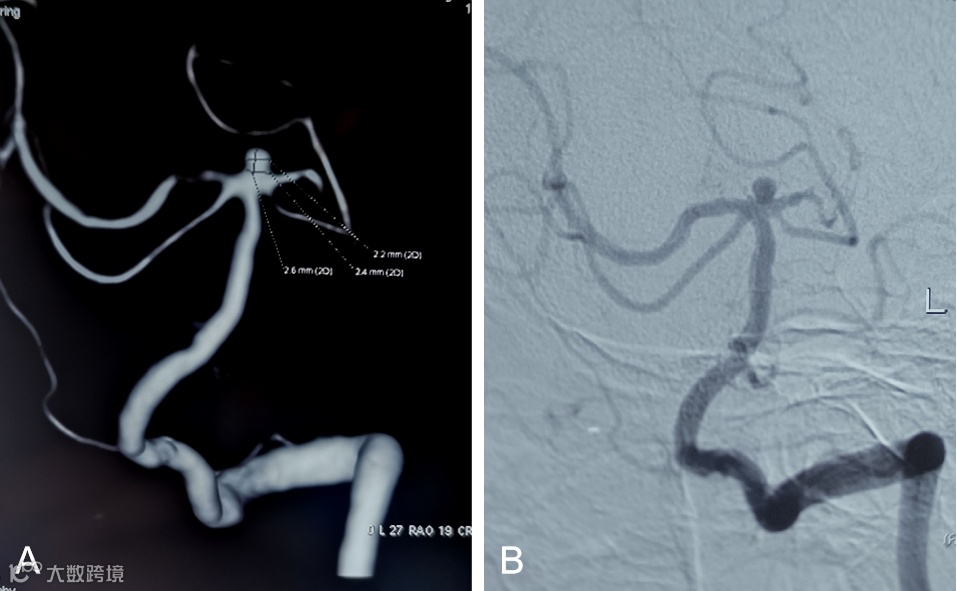

外院行头颅核磁示:右侧额叶脑梗塞(图1)

图1